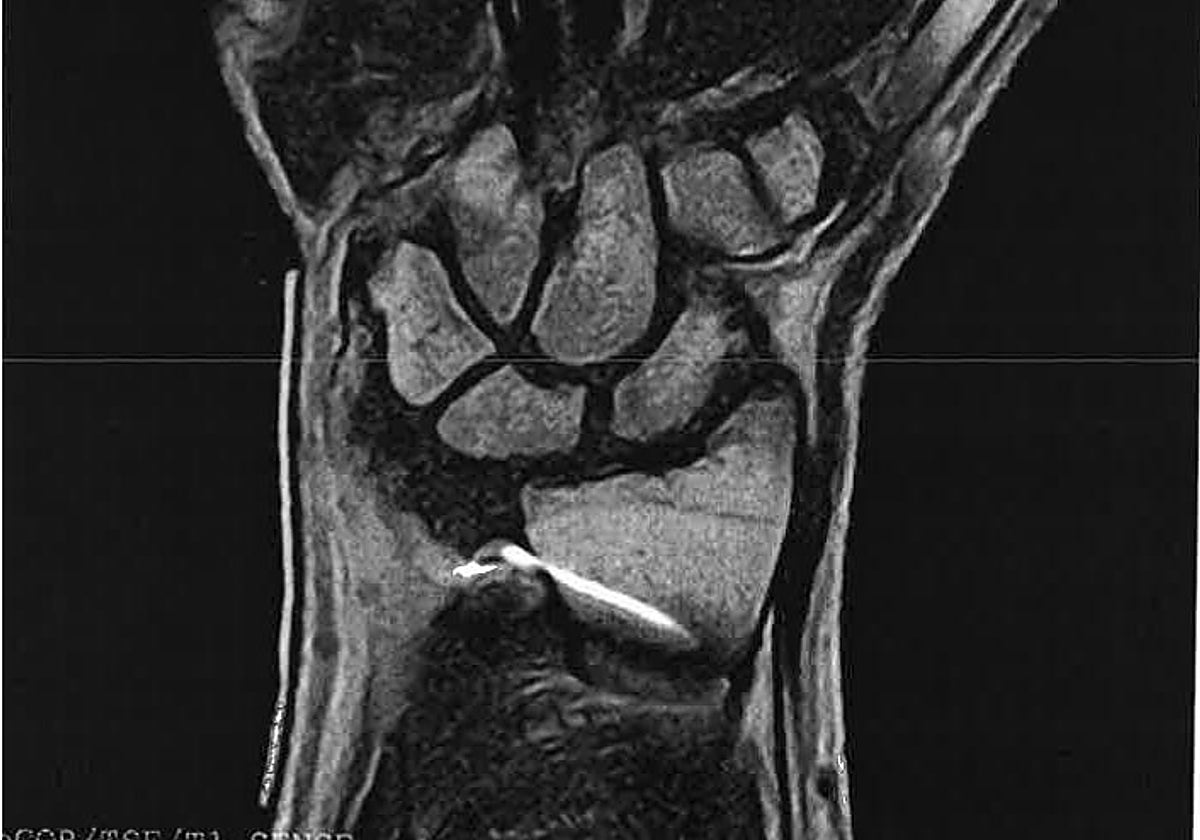

No fue hasta octubre de ese año -es decir, siete meses después- cuando se descubrió, en una resonancia magnética realizada precisamente por las molestias, que la paciente tenía dentro de su muñeca «un artefacto metálico probablemente por tratamiento de cirugía previa».

En la prueba se apreciaron daños en la articulación, en concreto una subluxación radiocubital dorsal, una rotura de ligamentos de la misma zona, rotura de la cápsula articular y erosión ósea, según el recurso contencioso-administrativo interpuesto por la paciente, representada en el procedimiento por el despacho de abogados Martín Fernández.

En noviembre de 2015, la mujer se sometió a una nueva intervención quirúrgica, realizada en la sanidad privada, para que le retiraran el fragmento de la aguja de K que se había quedado dentro de su muñeca tras la primera operación.